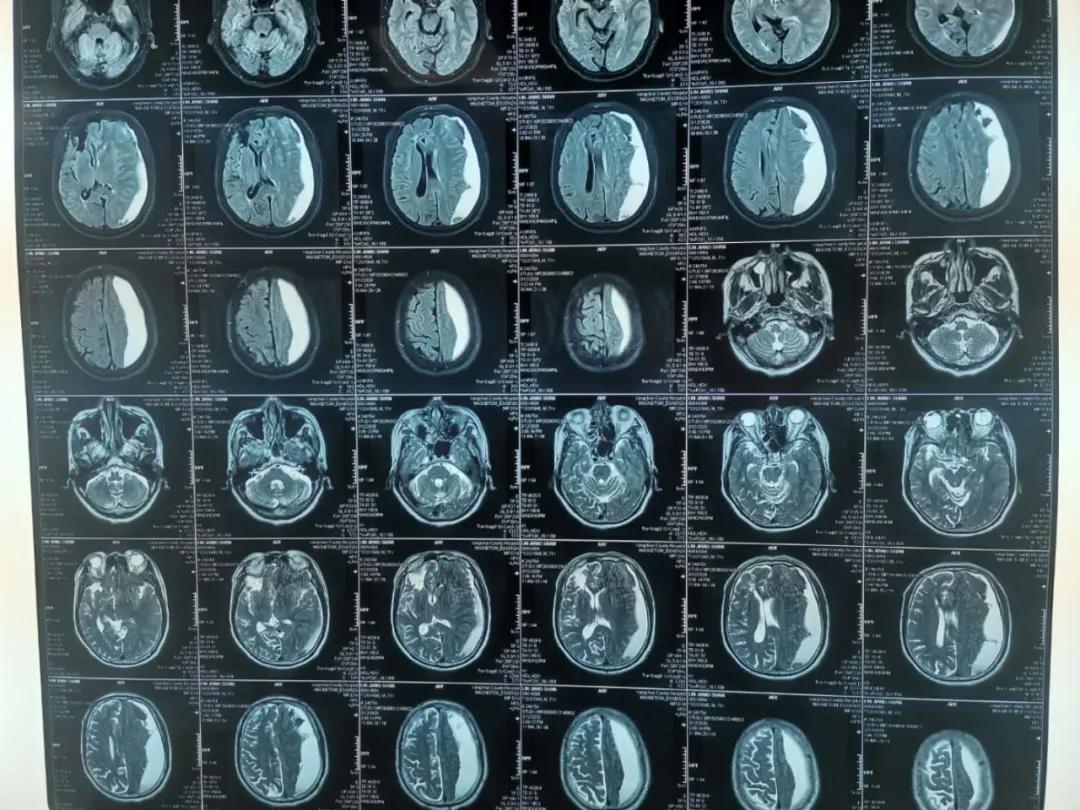

腔镜下颅内血肿清除术

患者林某,男性,82岁,反复头晕半个月,症状时好时坏,未引起重视,未进行治疗,4月27日突发右侧肢体无力,无不能言语,无人事不省,无口吐白沫、双眼上吊、四肢抽搐,无大、小便*禁失**。经查,该患者左侧额、颞、顶部亚急性硬膜下血肿,右侧顶部硬膜下少量出血未除。左侧额颞顶部硬膜下血肿清除术后,于2020.04.28在全身麻醉下行“内镜下颅内血肿清除术+脑积液漏修补术+颅骨修补术”。

术后降低颅内压及抗感染治疗,患者状态良好,病情得到恢复。

术前

术后